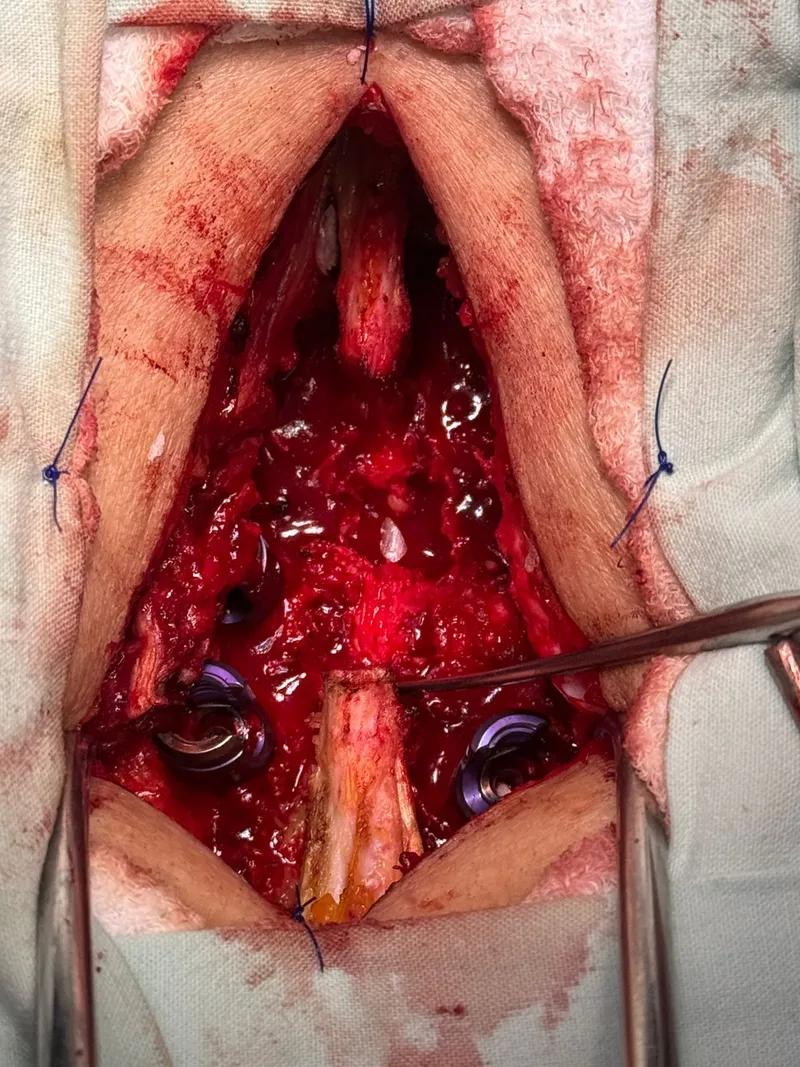

- Abordaje posterior: se realizó una incisión en la línea media de la espalda para acceder a las vértebras afectadas.

- Inserción de tornillos pediculares cementados: se colocaron los tornillos a través de los pedículos vertebrales, cada uno con inyección previa de cemento óseo para maximizar la fijación en el hueso osteoporótico.

- Conexión con barras: los tornillos se conectaron con barras metálicas que inmovilizan el segmento y permiten la fusión ósea.